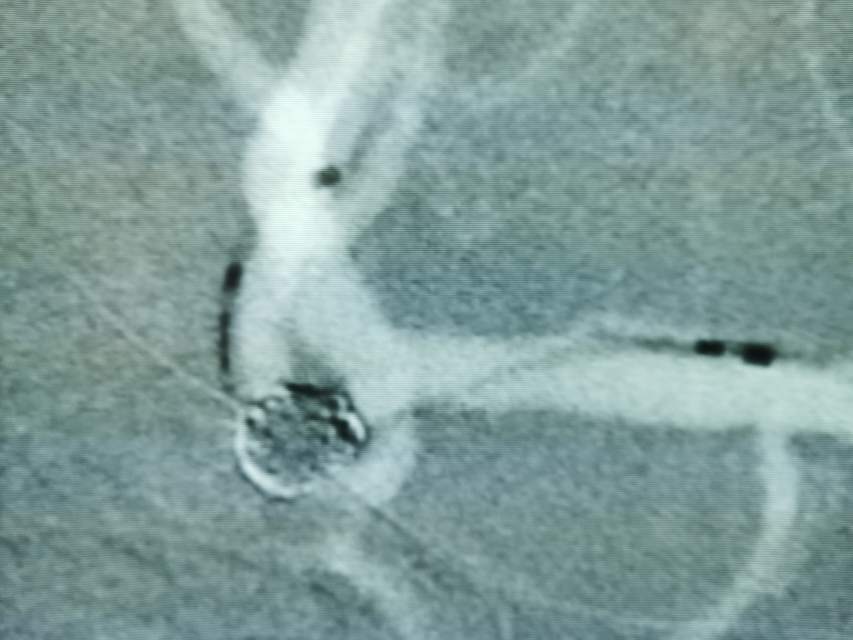

破裂的大脑中动脉动脉瘤二期支架植入

患者,中年男性,颅内动脉瘤破裂出血,急性期给予单纯弹簧圈大部致密栓塞(瘤颈少许残留),降低了急性期破裂出血的风险,急性期免除了使用抗血小板的顾虑和担心(如果使用支架),为了预防远期的复发,二期植入支架,就会安全多了